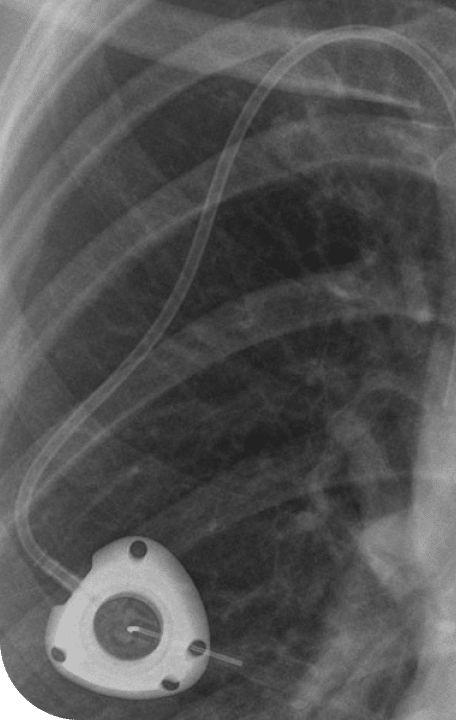

The PowerPort ClearVUE Implantable Port, marketed by Bard, is designed to be flexible and resistant to surface degradation and stress cracking. It is constructed from polyurethane plastic with a septum (needle access point) and a catheter that leads into a blood vessel.

Further, the device includes barium sulfate mixed into the plastic to make it visible on imaging. Once implanted, that additive can weaken structural integrity, increasing risks of degradation, fracture, or migration within the body. Some users have also experienced blood clots.

The catheter is made from a type of polyurethane and silicone. It contains barium sulfate, a contrast dye that makes the port more visible during imaging tests, such as X-rays and CT scans. Unfortunately, barium sulfate has been shown to degrade polyurethane and silicone when in contact with human tissue.